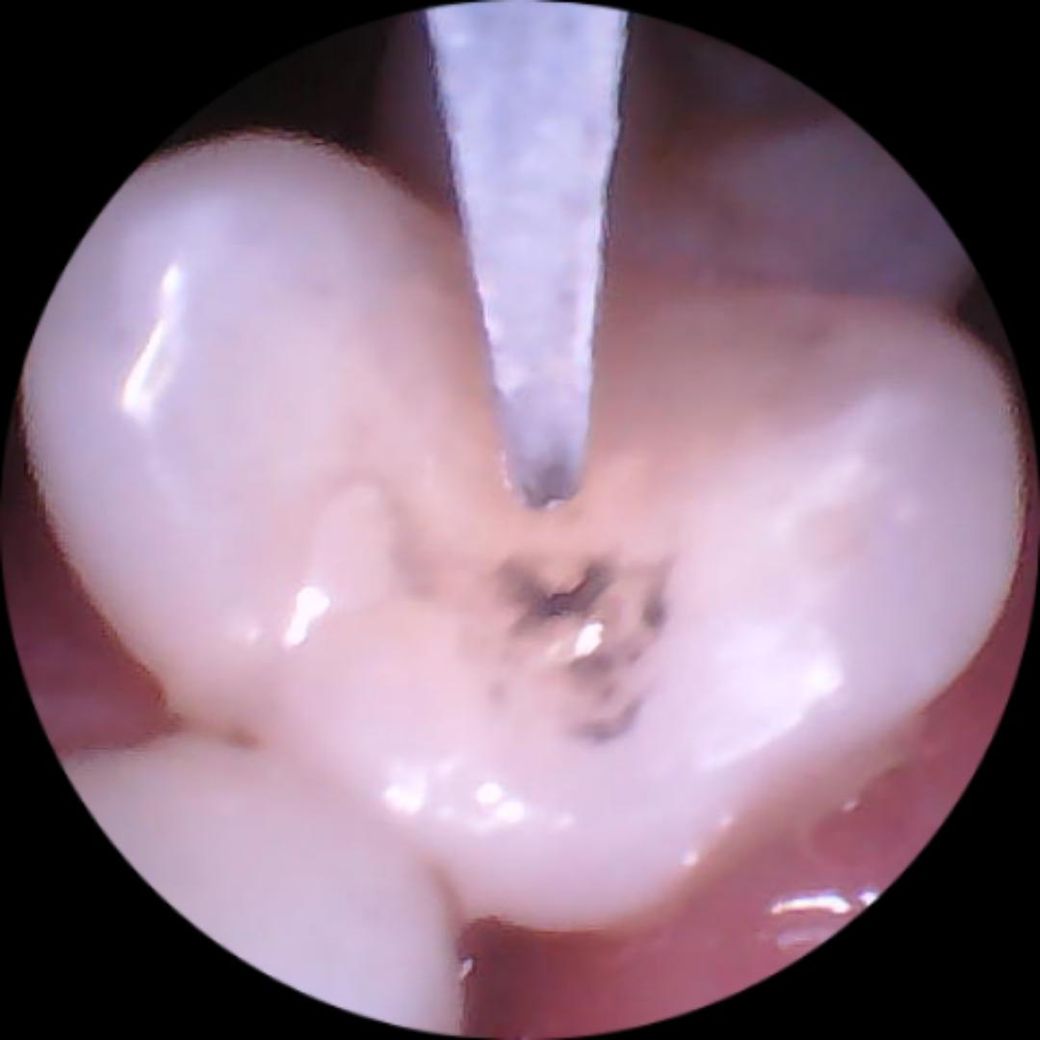

치석제거기로 레진 때운 부위를 살짝 갈았더니 시커먼 먹물같은게 나와요

두달전에 충치가 생겨 레진으로 때웠었는데

갑자기 때운치아가 너무아파 집에있는 셀프 치석제거기로

레진때운 경계 부위를 살짝 갈았더니

먹물처럼 시커먼게 나오고 껌같은 하얀색도 좀보여요

이게 뭘까요 의사가 충치제거를 제대로 안해서

충치가 검은색으로 나오는 건가요?

• 1번 째 사진